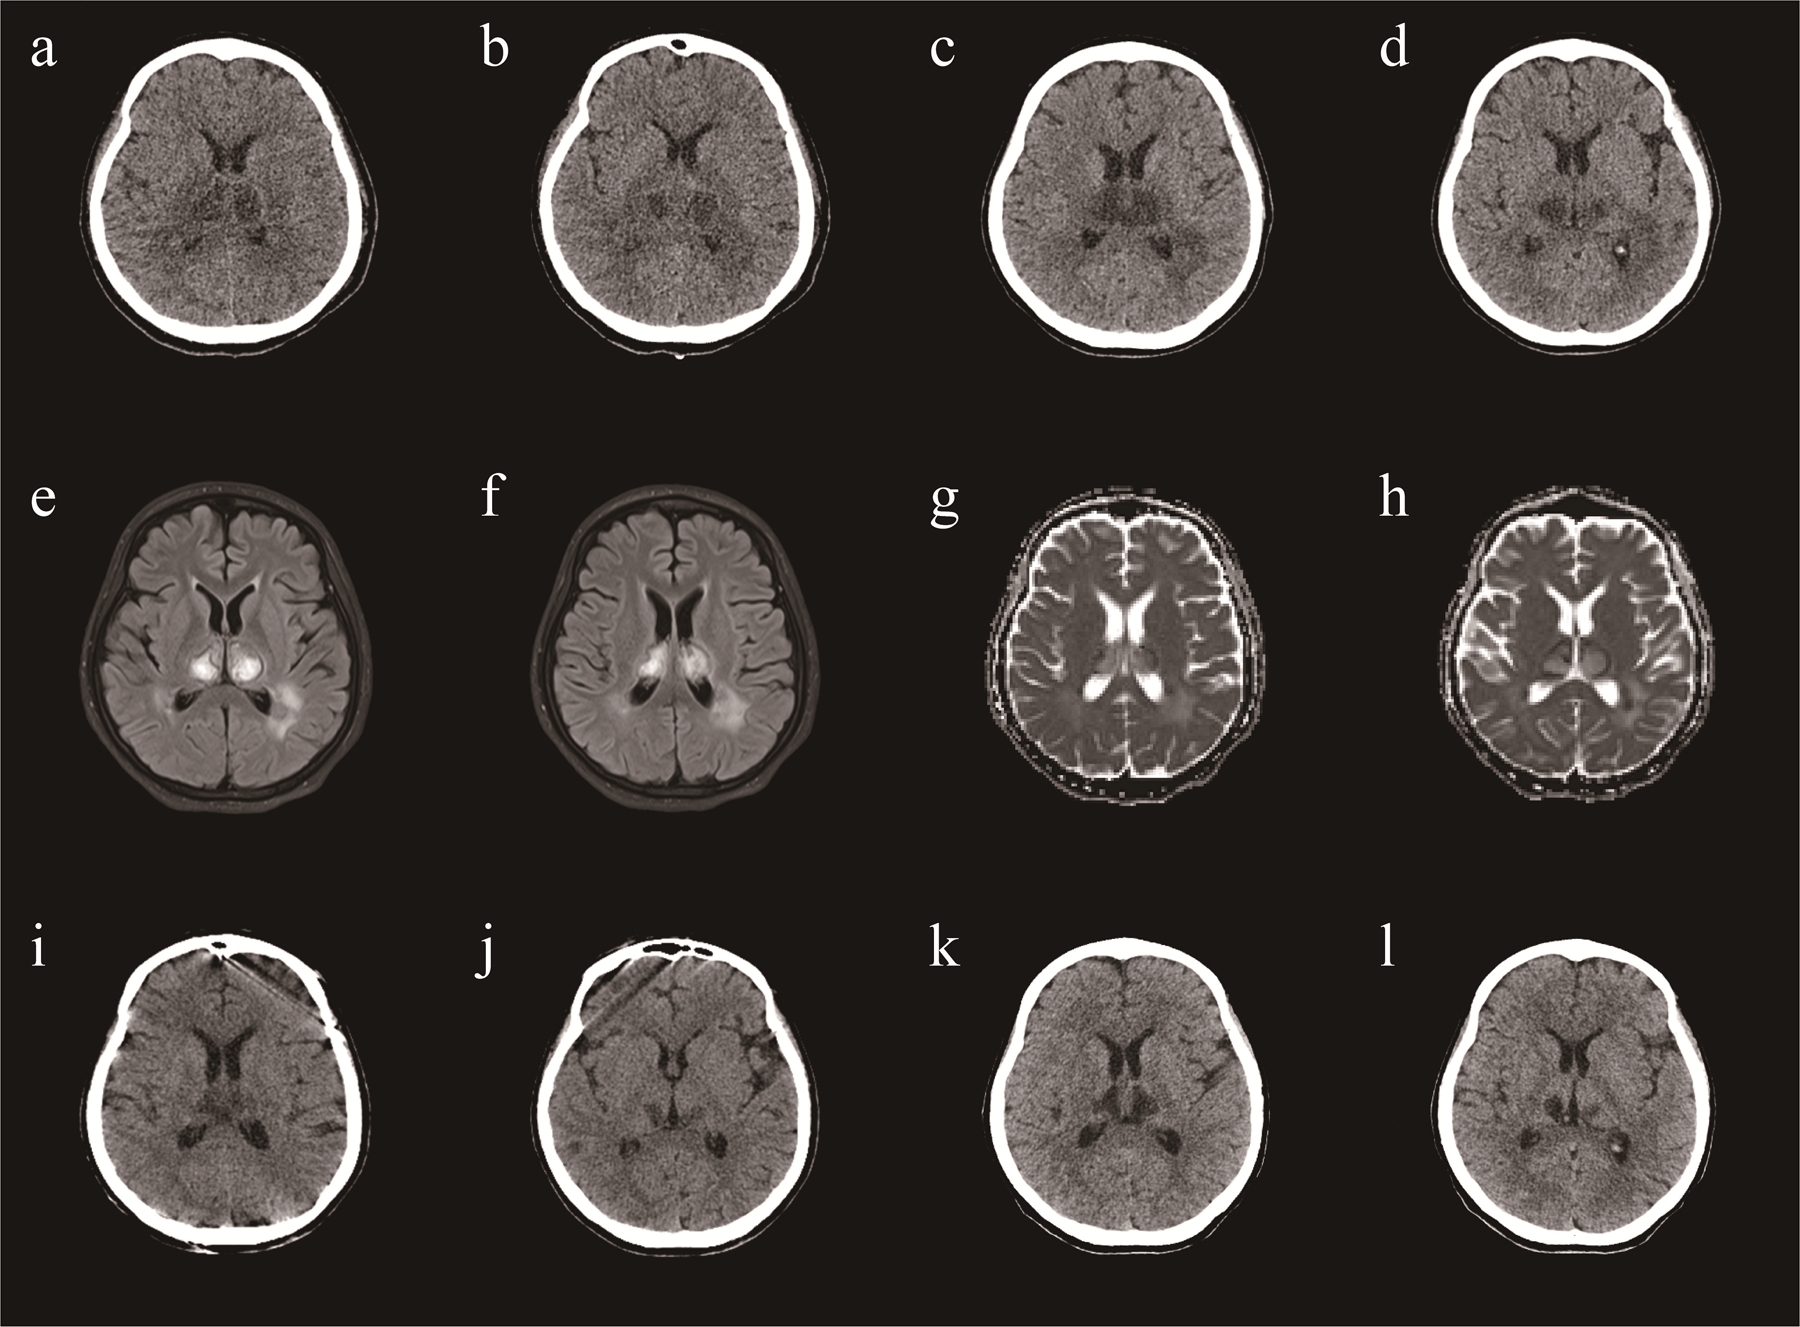

Brain Computed Tomography (CT) and Magnetic Resonance Imaging (MRI) revealed lesions involving the bilateral striatum, thalamus, and brainstem, typical for ANE (Figures 1A,B,I–L). A diagnosis of ANE accompanied by fulminant myocarditis was considered. Therefore, tocilizumab was included in the treatment regimen. Tocilizumab was used in hospital day 9 (8 mg/hg of tocilizumab for 1day). On the tenth day of admission, the patient began to regain consciousness. She was transferred to a general ward after 13 days. Echocardiography showed a significant improvement in left ventricular function (EF = 61%). The patient was discharged after approximately 24 days of rehabilitation. At the time of discharge, the patient could walk and speak clearly. She was discharged with a prescription for cardioprotective agents, including metoprolol, sacubitril/valsartan, spironolactone, furosemide, and dapagliflozin. One month after discharge, the patient was able to walk on her own, her speech was cleared, there were no remaining symptoms, and her heart function was normal. A repeat CT revealed that the lesions in the head had reduced (Figures 1G,H).

Figure 1

A brain CT (a,b) demonstrating symmetric lesions involving thalami, striatum and brain stem, consistent with acute necrotizing encephalopathy in day 12. A repeat CT revealed that the lesions in the head had reduced (c,d) in day 20. A repeat CT revealed that the lesions in the head had reduced (e,f) in day 38. One month after discharge, a repeat CT revealed that the lesions in the head had reduced (g,h). MRI (i,j) demonstrating symmetric lesions involving thalami, striatum and brain stem, consistent with acute necrotizing encephalopathy in day 22.